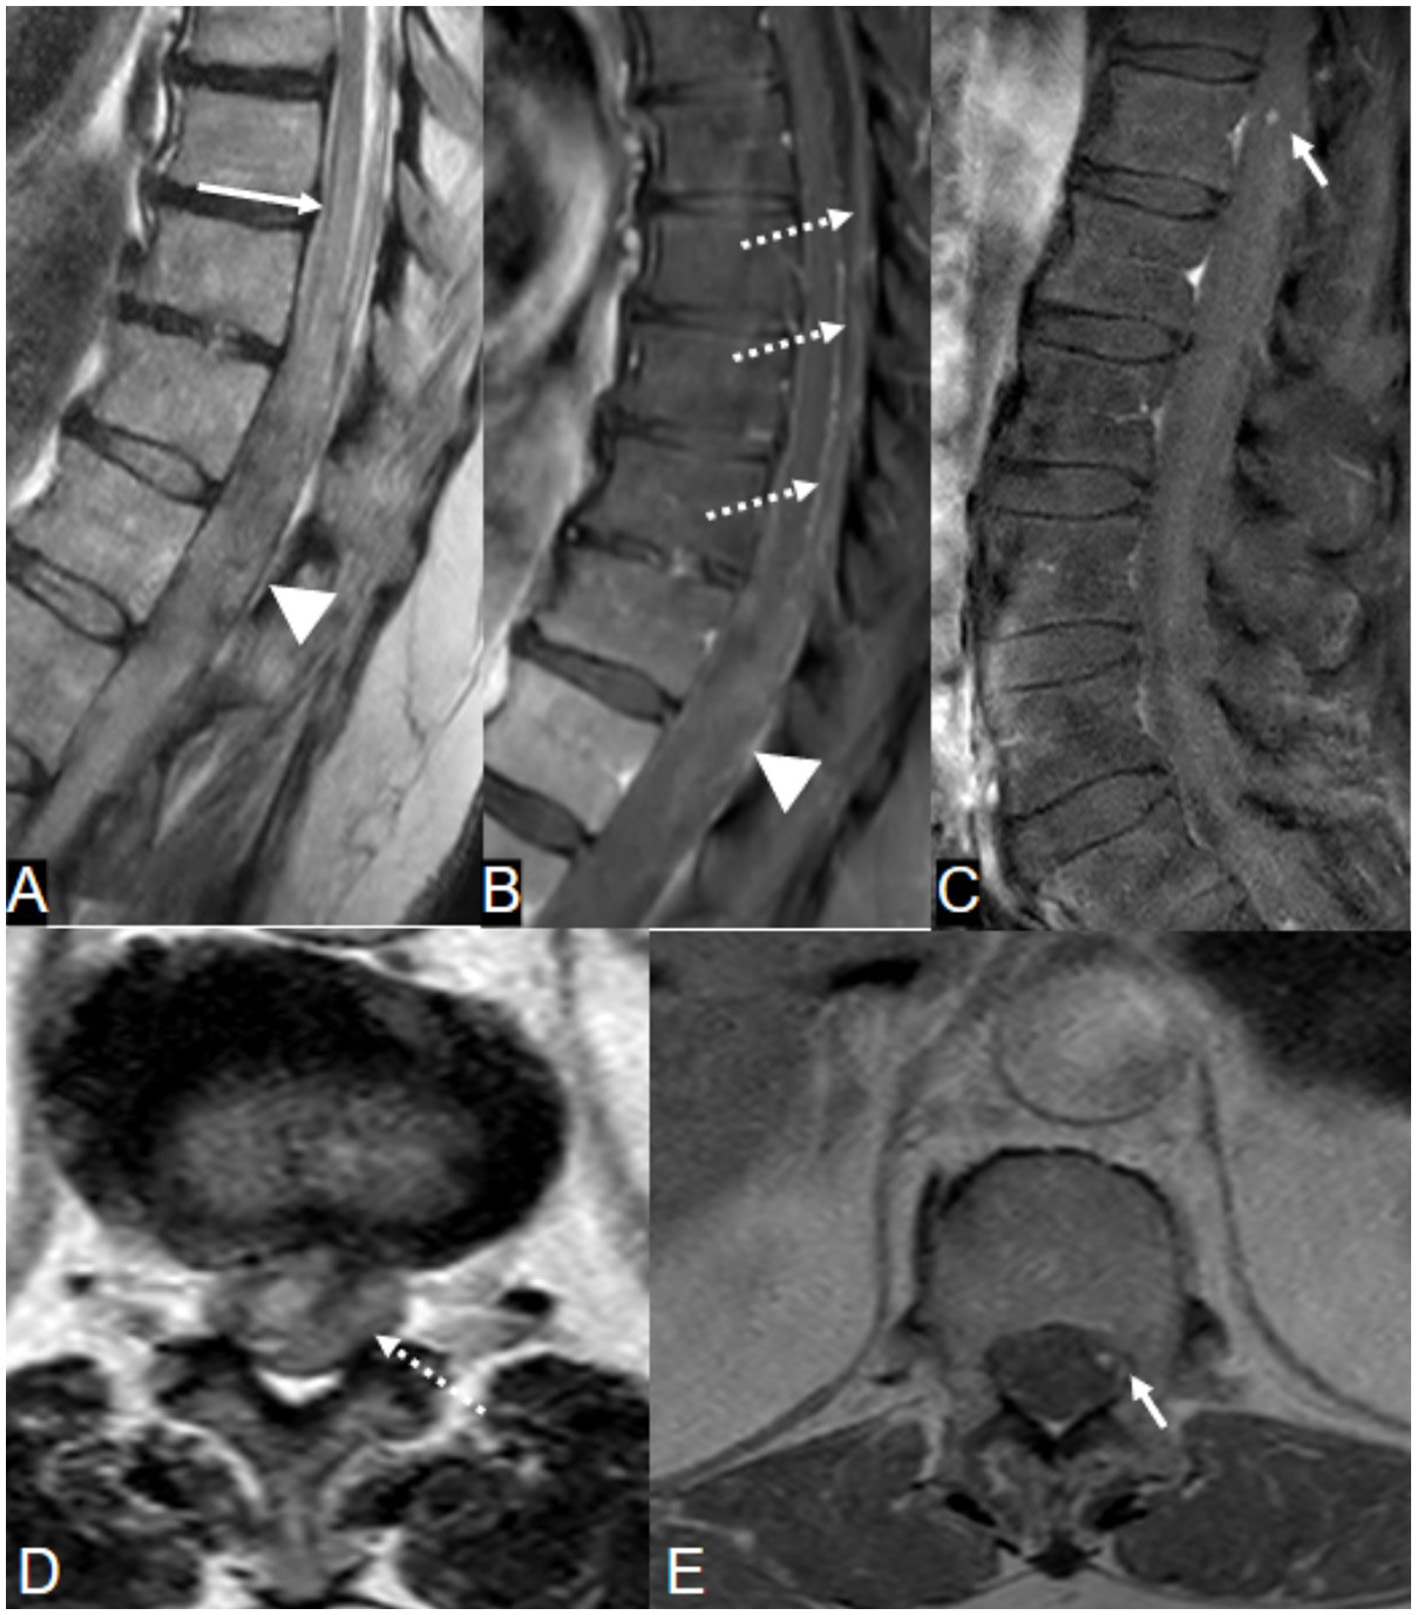

Magnetic resonance imaging (MRI) of the spine (Figure 1) demonstrated a subdural hematoma with spinal cord edema along the lower cervical and upper thoracic spine, with SAH tracking down to T9 level. On postcontrast T1-weighted sequences, there was focal nodular enhancement within the hematoma at the level of T2. The patient underwent a spinal angiogram, which demonstrated a fusiform dilatation of the right PSAs originating at the T2 level consistent with an ISAA.

A 60-year-old woman presented with acute back pain and flaccid quadriparesis. A, B: Sagittal T2-weighted MRI images of the spine [(A) cervical spine and (B) thoracic spine] show a subdural hematoma extending along the lower cervical and upper thoracic spine, and spinal subarachnoid hemorrhage extending down to the level of T9. Note associated cord edema. (D, E) Axial T2-weighted (D) and gradient echo (E) images demonstrate the SDH centered predominantly along the right side of the spinal canal (arrowheads), displacing the cord to the left. (F) Postcontrast T1-weighted image shows focal nodular enhancement within the subdural hematoma (arrow), corresponding to a fusiform “tent-like” dissecting aneurysm arising from the right T2 radiculopial artery on spinal angiogram (C, arrow). This was surgically resected and characterized by histology as an organizing hematoma.